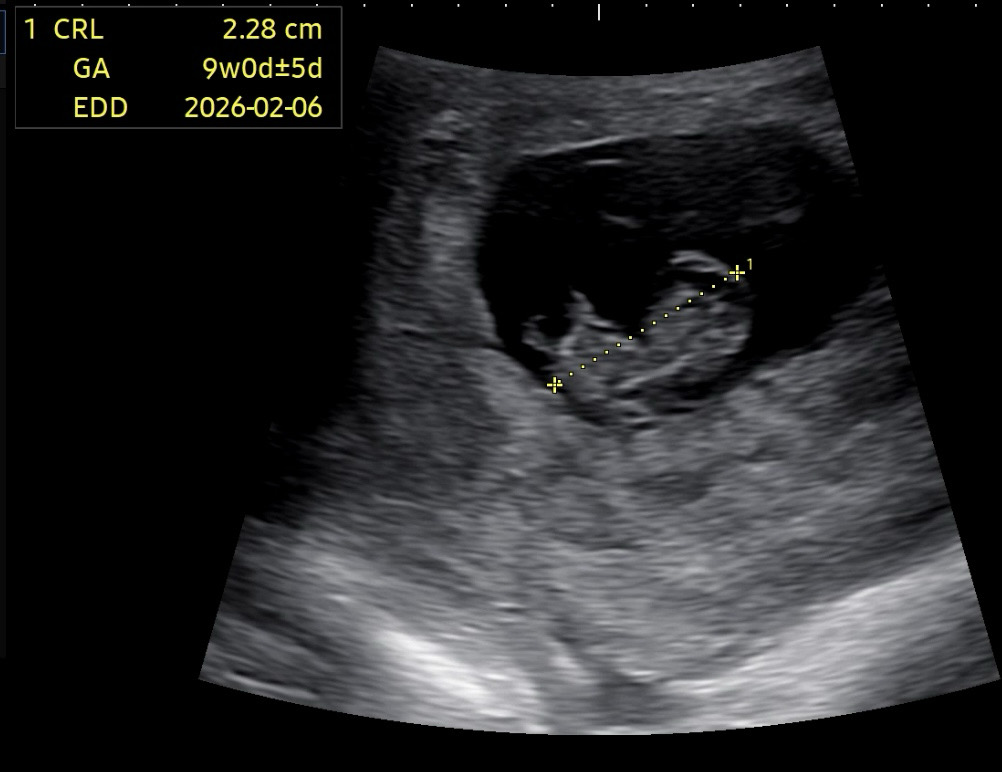

젤리곰 지난걸까요?

오늘 하리보 기대했는데 팔다리 똥그란 시절은 끝났나봐요 ㅎㅎ 임신 실감 안났는데 올때마다 쑥쑥 자라는 모습에 놀라요 ㅎㅎㅎ